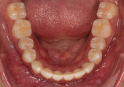

Classe II div 1, articulé croisé postérieur, surplomb accru, déviation de la ligne médiane maxillaire, rotations d'encombrement

Résultats obtenus

- Articulé postérieur corrigé

- Courbe de Spee nivelée

- Forme de l'arcade améliorée

- Des arcades harmoniques ont été obtenues

- Forme d'arcade ovale

- L'expansion molaire supérieure et les taquets multi-plans optimisés pour la rotation de la deuxième molaire inférieure ont été utilisés pour la résolution de l'occlusion croisée postérieure gauche

État initial

État final